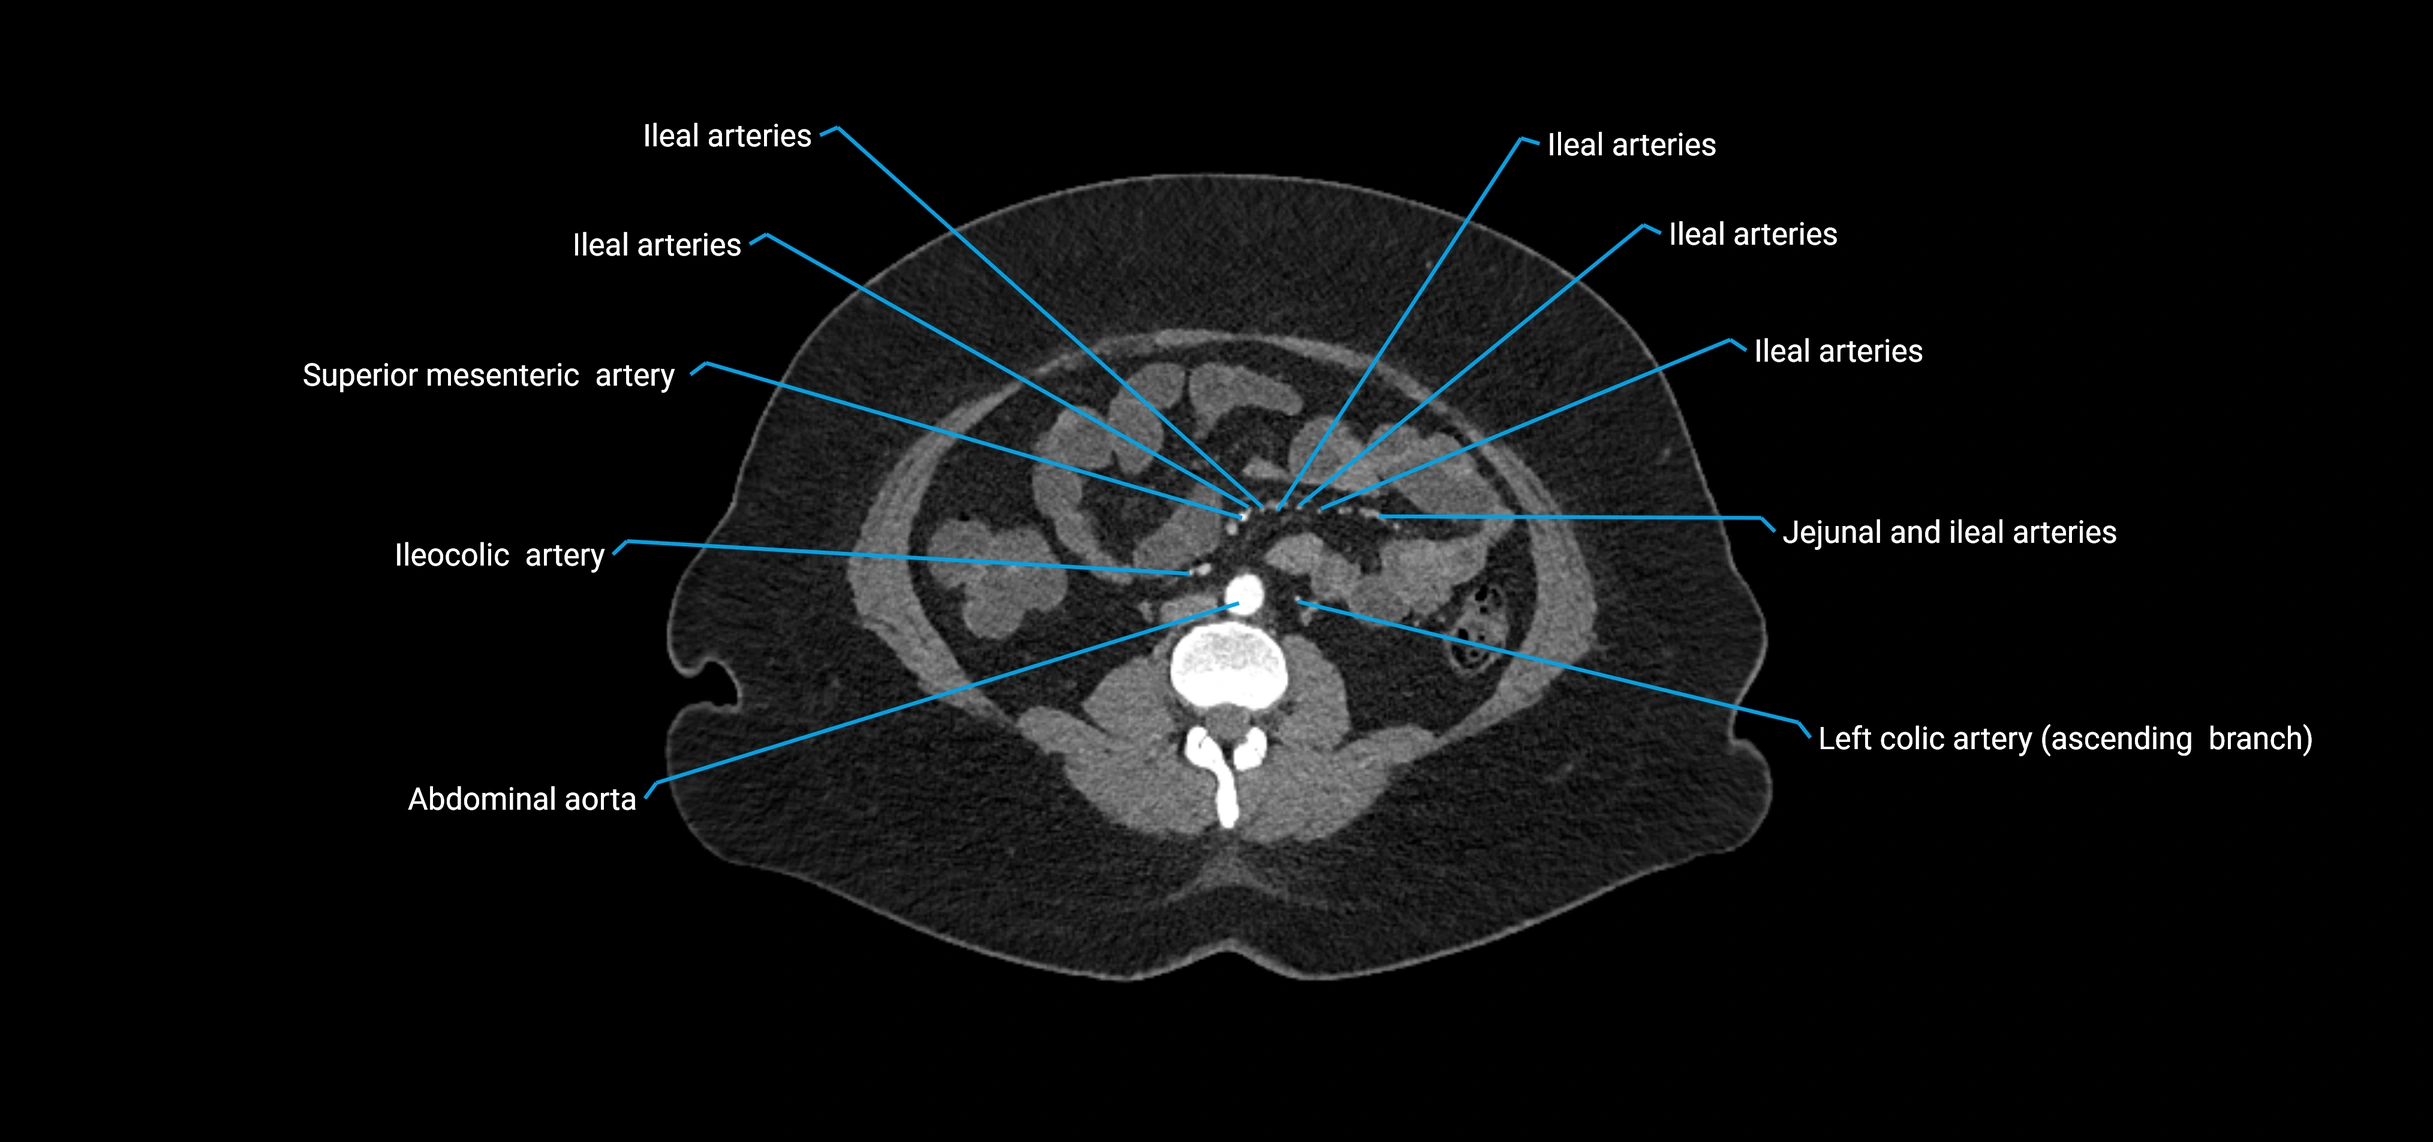

Contrast-enhanced CT (CTA):

• Gold standard for abdominal aortic imaging

• Provides excellent detail of lumen, wall, aneurysm, thrombus, and branch vessels

• Multiplanar and 3D reconstructions help in aneurysm measurement, stent graft planning, and dissection evaluation

• Detects acute rupture, traumatic injury, or occlusion with high sensitivity